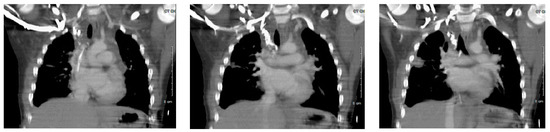

Figure 2.

Chest computed tomography (CT) (intravenous (IV) contrast) scan demonstrating inability to fully visualize the superior vena cava (SVC) in total, and no opacification of the right internal jugular (IJ). Images from left to right demonstrate CT slices in an anterior to posterior fashion, respectively.